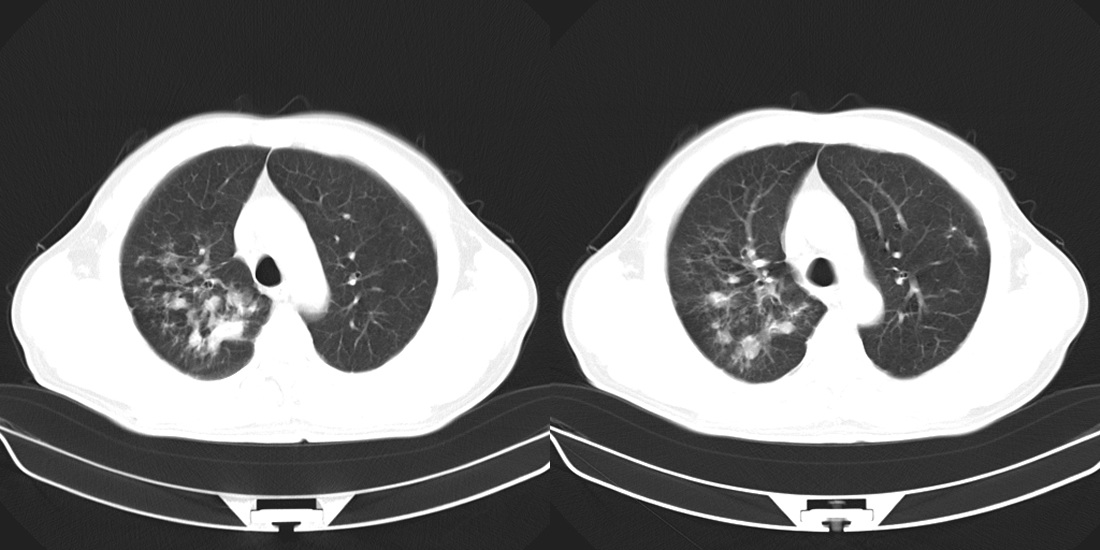

标题: CT10251:男性56岁,结核球? [打印本页]

标题: CT10251:男性56岁,结核球?

56岁男性,低热、消瘦,曾x线诊断肺结核。

两肺结核,左肺结核球。

双肺结核伴左上肺结核球形成

两肺多形性病变,支持肺结核.

两肺多形性病变,且在结核好发部位。支持肺结核.